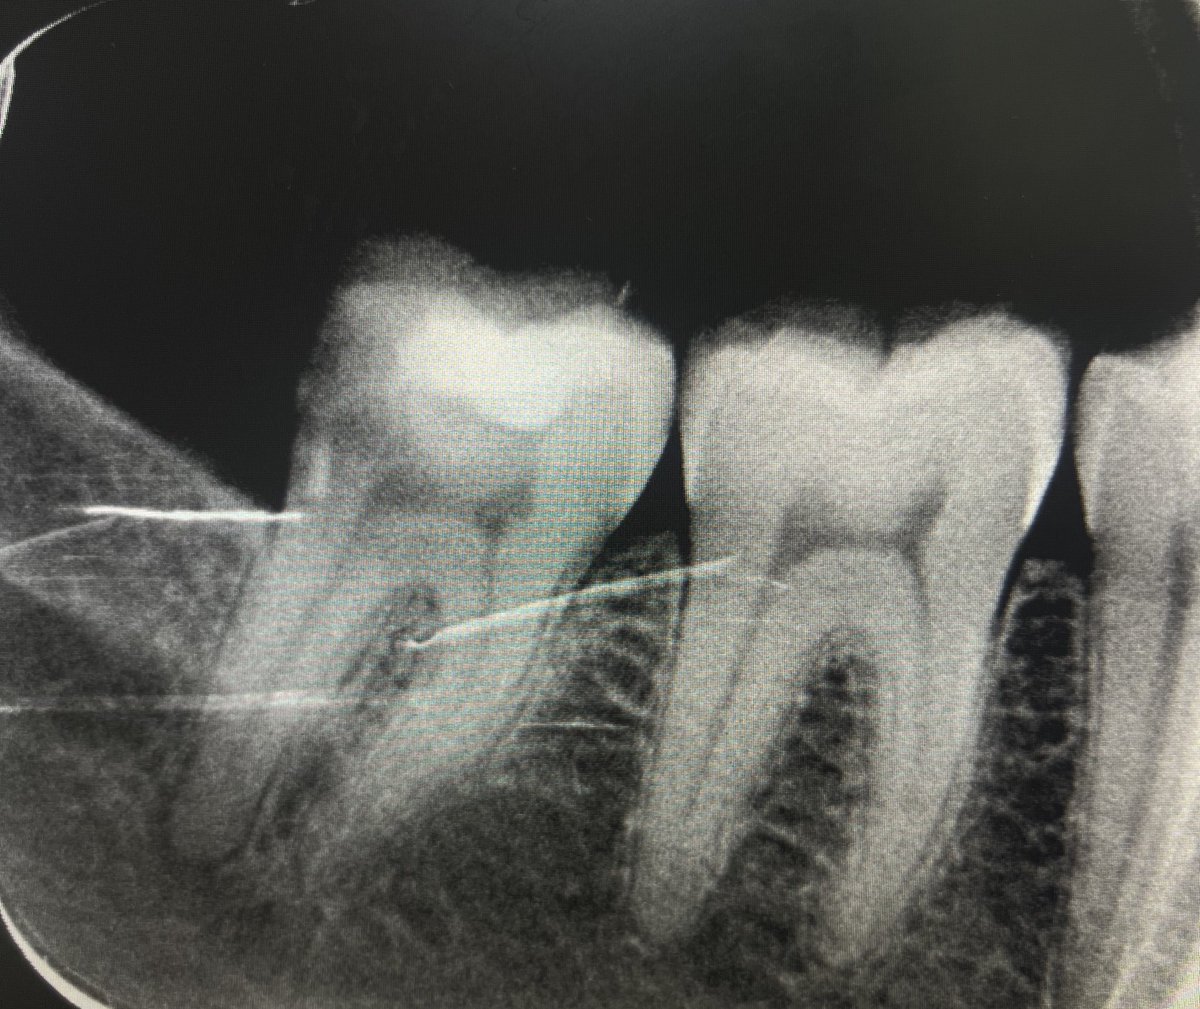

حالة جديدة اليوم ❤️

Root Canal Treatment for #36

The patient complained of severe pain,after examination we decided to do RCT.

Dx: SIP,NAP

ML wall is replaced then started RCT.

Single Cone and BC Sealer are used

✅✅